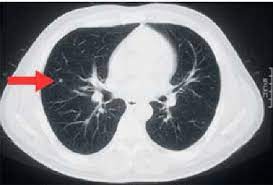

Can You Detect Lung Cancer With Ct Scan - Detection Of Early Stages Of Lung Cancer Based On Imaging A Download Scientific Diagram - Your doctor might use imaging tests to look for unusual growths inside your body that might be cancer.. It can also show whether the cancer has spread outside the lung. It gives detailed information about your cancer. Ct scans of the chest are used to find lung nodules or other chest pathology. Therefore, ct scans can lead to a false negative this can negatively impact your ability to get any treatment at all If cancer is diagnosed, other tests will be performed to stage and grade the tumor so that the appropriate treatment can be delivered.

Once a nodule is found, a workup is done to see if it is cancer. This can include a chest computed tomography (ct) scan and, if a nodule or mass is found, a biopsy. A ct scan is one of several diagnostic tests that physicians order when they suspect lung cancer. The amount of radiation you're exposed to during an ldct is much less than that of a standard ct scan. If the test finds cancer, treatment can start early.

A ct scan test can also be used to look for the spread of lung cancer in the adrenal. Once a nodule is found, a workup is done to see if it is cancer. It is used to look for early signs of lung cancer. Ct scans of the chest are used to find lung nodules or other chest pathology. Awareness of the possible causes of overlooking a pulmonary lesion can give radiologists a chance to reduce the occurrence of this eventuality. This can provide definitive evidence of the disease. If you are a smoker, it is highly recommended to have a ct scan every 3 months. It gives detailed information about your cancer. It's equal to about half the radiation you're exposed to naturally from the environment in a year. Another doctor might be able to recommend other testing options. Your doctor might use imaging tests to look for unusual growths inside your body that might be cancer. Computed tomography (ct) scans detect tumors, but do not determine whether they are malignant or not. The doctor will then order additional testing to rule out or confirm a cancer diagnosis.

But the test is not helpful for light smokers or people who quit smoking more than 15 years ago. Early detection of lung cancer means more treatment options an excellent tool for people at high risk for lung cancer the scan is quick, painless and noninvasive ct imaging is detailed and accurate and can reveal the smallest of abnormalities The scan looks at your lungs and other parts of your chest. Ct is highly accurate for lung cancer detection. Nevertheless, lung cancer can also be overlooked on computed tomography (ct) scans, regardless of the context, either if a clinical or radiologic suspect exists or for other reasons. A ct scan test can also be used to look for the spread of lung cancer in the adrenal. If you are at higher risk, talk to your doctor about getting screened. The smallest recesses of the chest can be clearly seen. It can also show the size, shape, and position of any lung tumors and can help find enlarged lymph nodes that might contain cancer that has spread. Therefore, ct scans can lead to a false negative this can negatively impact your ability to get any treatment at all Ct scans of the chest are used to find lung nodules or other chest pathology. Alternatively, you should take lung ct scans if you are concerned or if you show any symptoms. It can also look at your liver and adrenal glands.

Ldct scans can help find abnormal areas in the lungs that may be cancer. It can also look at your liver and adrenal glands. It can show the size, shape, position, and depth of any lung tumor. Nevertheless, lung cancer can also be overlooked on computed tomography (ct) scans, regardless of the context, either if a clinical or radiologic suspect exists or for other reasons. Ct is highly accurate for lung cancer detection.